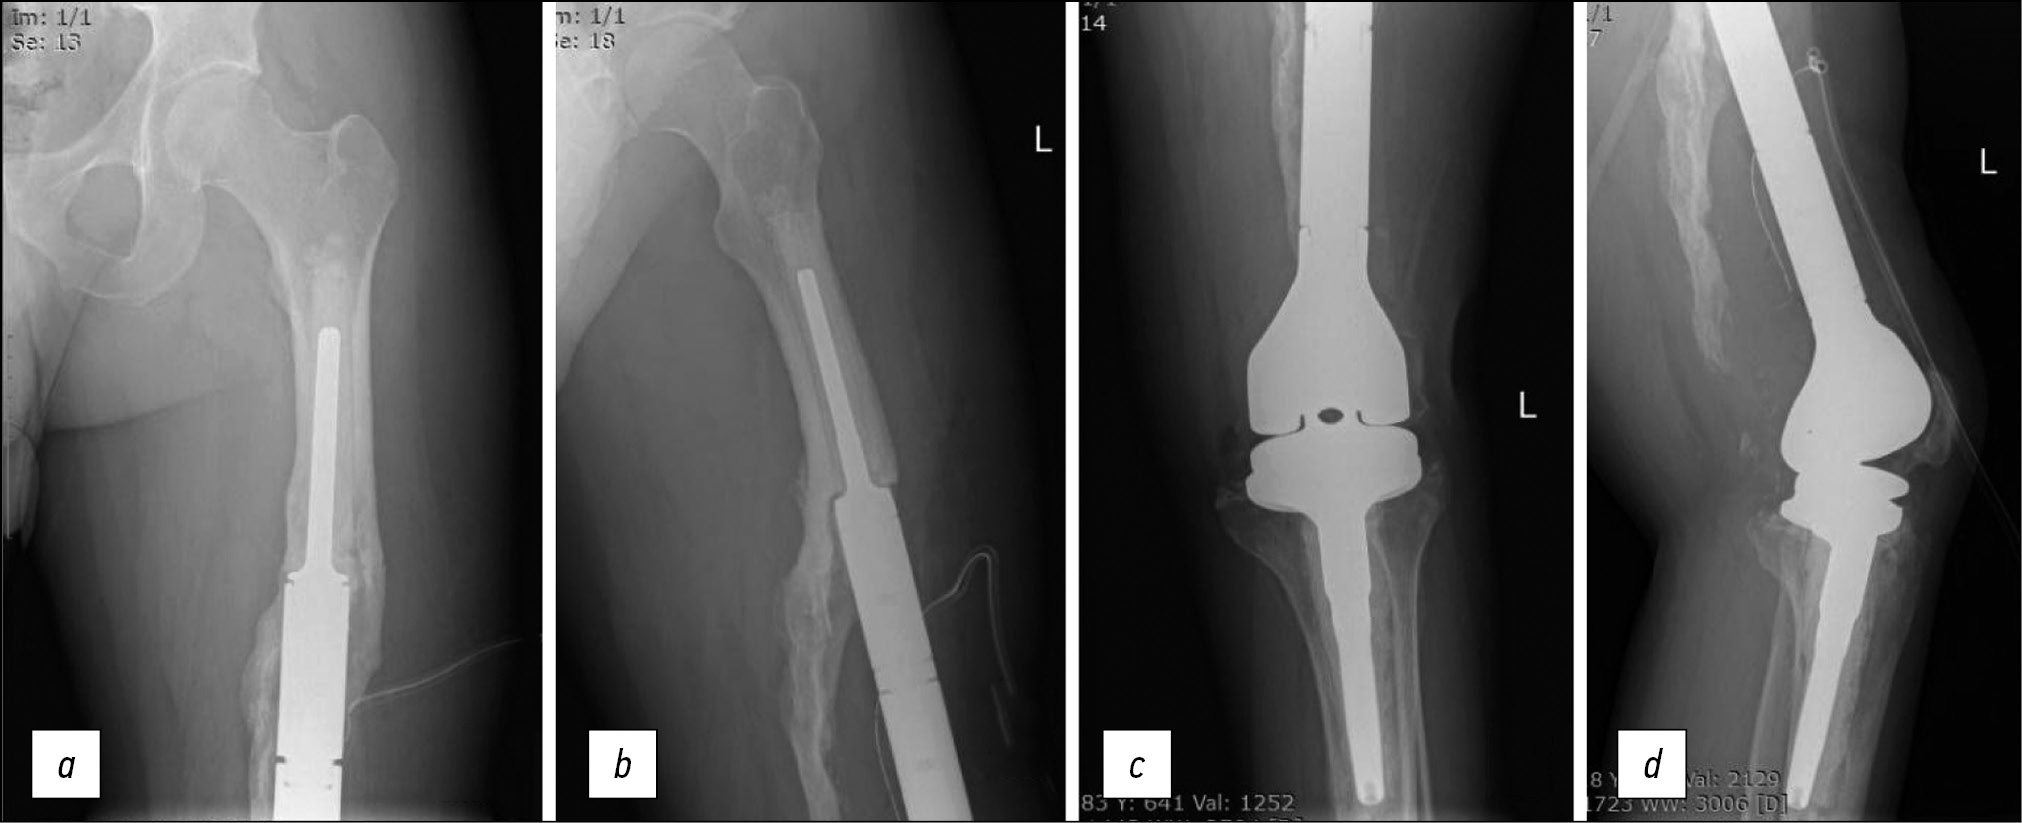

On March 12, 2015, the distal part of the left femur with endoprosthesis was resected (Fig. 5). A modular hybrid endoprosthesis by Stryker (MI, USA) was placed, which included the cementless femoral stem of the endoprosthesis and the cemented tibial stem.

Fig. 5. Radiography after primary endoprosthetics in 2015: a — femoral stem of the endoprosthesis, frontal projection; b — femoral stem of the endoprosthesis, lateral projection; c — tibial pedicle of the endoprosthesis, frontal projection; d — tibial pedicle of the endoprosthesis, lateral projection.